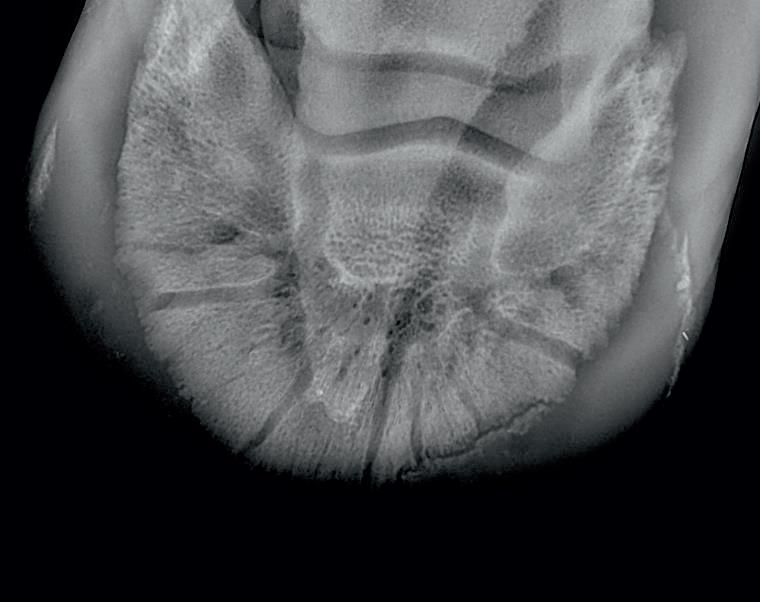

Here is a veterinary radiographic report on a horse with a fracture evident on the medial toe and after treatment and feeding Bone Gold during this period. More information on these products can be found at www.vetgold.com.au

XXXXXXX's left and right front feet were radiographed on 26th Aug, 21st Oct (8 weeks) and again on the 17th Nov '21(12 weeks).

XXXXXXX’s left and right front feet were radiographed on 26th Aug, 21st Oct (8 weeks) and again on the 17th Nov ‘21(12 weeks).

26.08.21: Right Front: Large P3 solar margin fracture evident on medial toe 32.6mm x 4.1mm with approximately 1.4mm separation from parent bone as below left image.

21.10.21: Right Front: Fine residual 4.2mm fracture still evident, approximately 90% resolution

17.11.21: Right Front: Fracture fully resolved

26TH AUG 21

21ST OCT 21

Radiographic results as of the 17th Nov '21 show total resolution of the original fracture.

XXXXXXX was reshod today utilising off an alloy shoe with a toe clip - inner circumference seated out to avoid any sole pressure. The horse can return to training.

Solar margin Type IV fractures of this magnitude have well-documented internationally published healing rates of 7 - 12 months. Full resolution of these fractures is rare as most often the fracture fragments are resorbed. Full resolution in a 3 month period was not anticipated.

The horse was on Bone Gold 3 x scoops fed once per day for this period.

26th August 2021 21st October 2021 17th November 2021